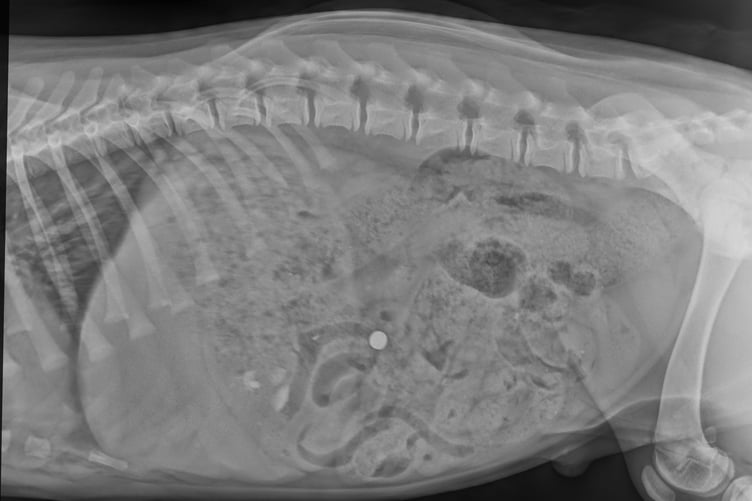

He was rushed off to St Peter’s Vet in Petersfield and following the X-ray surgeons were able to see the battery had travelled through his stomach and into his intestines.

“We made an incision in Warrior’s abdomen, but although the battery could be seen clearly on the X-ray, it proved tricky to find because a dog’s intestines are quite long and the battery was tiny – it only measured about 1cm across.